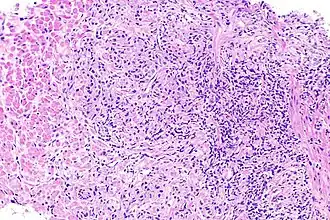

Изредка встречается также не упомянутый в этой классификации хронический гранулёматозный простатит.